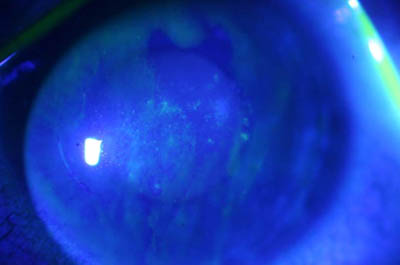

Aspecto Clínico

- Superficie corneal irregular y grisacea

- Opacidades granulares en parche

- Formación de lineas epiteliales elevadas de aspecto granular, que pueden dar imágen de seudodendritas

- Opacidades superficiales satélites

- Ulceración epitelial variante

- Formación de anillo inmunológico

Superficie corneal irregular y grisácea

Opacidades granulares en parche

Opacidades superficiales satélites

Ulceración epitelial variante